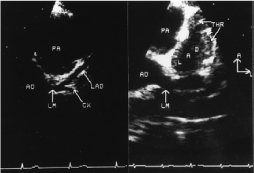

Figure 5. Showing coronary angiogram, and echocardiogram from the same patient with coronary aneurysm.

Figure 6. Echocardiographic images from normal subject and from patient with KD.Left, Normal patient: Parasternal short-axis echocardiographic visualization of the left main [LM], left anterior descending [LAD], and circumflex [CX] coronary arteries. AO indicates aorta; PA, pulmonary artery. B, Kawasaki patient: Parasternal short-axis view demonstrating thrombus [THR] in the LAD. Orientation: A, anterior; L, left. [66].